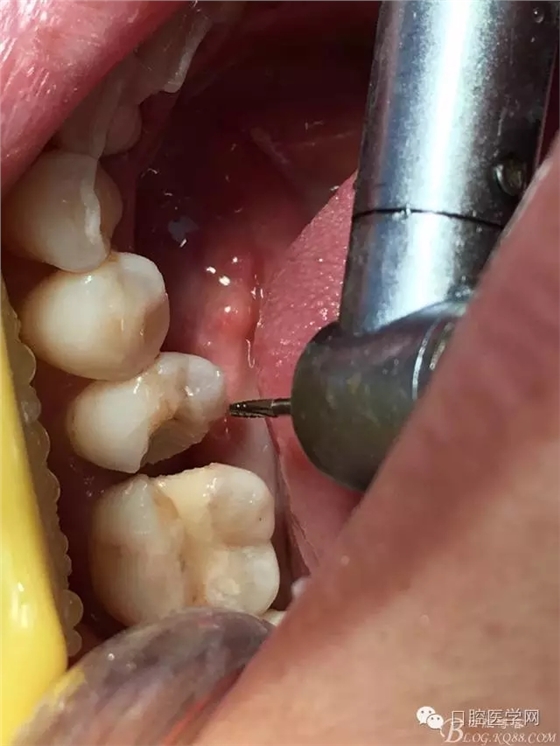

去除 D5遠(yuǎn)中不良充填物并去腐

D5消毒,隔濕,放入楔子,進(jìn)行玻璃離子充填